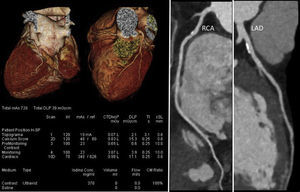

In daily clinical practice, it is not uncommon to identify athletes with a higher than expected atherosclerotic burden. Figure 5 illustrates a CCTA of an asymptomatic 47-year-old male competitive Ironman athlete, with a discrepancy between total CV risk based on SCORE (<1%) and extent of CAD.38

Coronary computed tomography angiography of a competitive Ironman veteran athlete with low cardiovascular risk based on SCORE (<1%), but with a higher than expected atherosclerotic burden (calcium score >percentile 90), with plaques in all the epicardial coronaries, including >5 segments with plaque (segment involvement score >5) and involvement of the left main and proximal left anterior descending arteries (adapted from Dores et al.38).